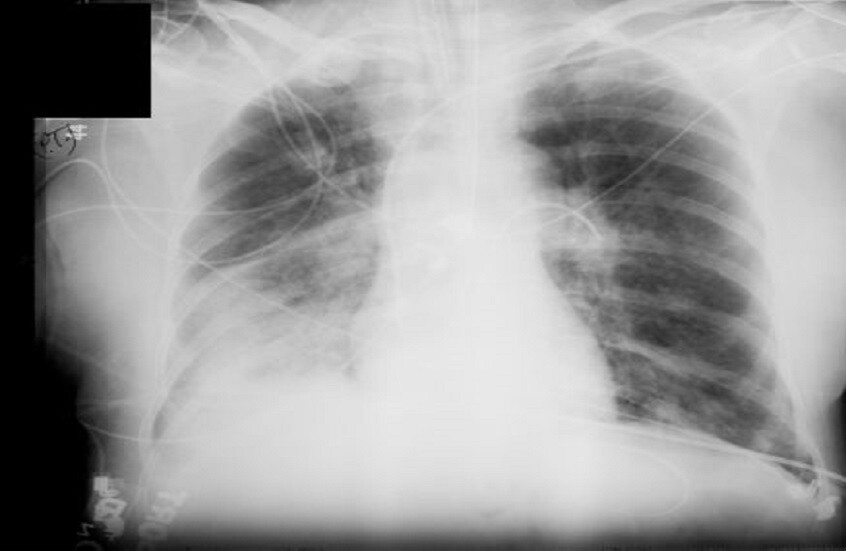

أفادت الدكتورة أوكسانا بلاتونوفا أخصائية الأشعة، أن الأشعة السينية لا تزال أداة تشخيصية مهمة، ولكن لا تزال المخاوف تحيط بها.

وتؤكد بلاتونوفا، أن عدم اكتشاف المرض أخطر بكثير من الخضوع للأشعة السينية، حيث المعدات الحديثة تقلل من المخاطر، كما أن الفحوصات في الوقت المناسب تسمح بالكشف السريع عن الأمراض وبدء العلاج.